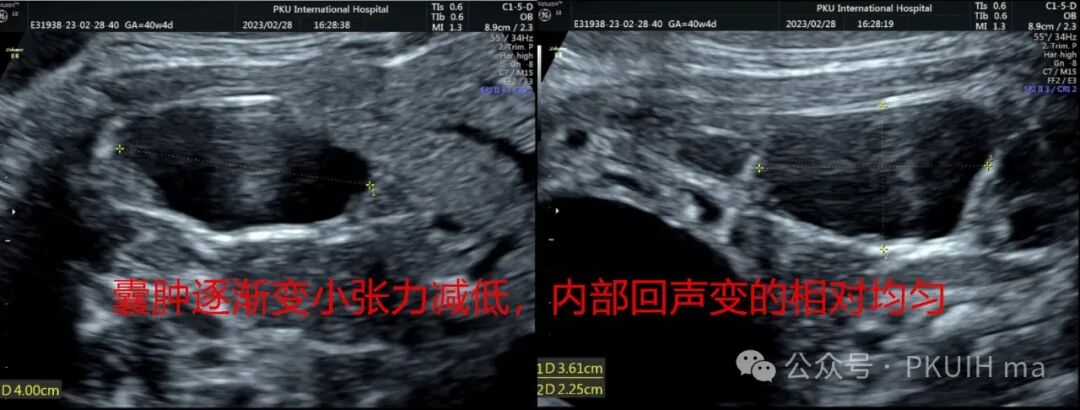

在随后的随访观察中(如下图)发现囊肿大小和内部回声有变化。最终考虑是卵巢出血性囊肿(卵巢扭转待除外)